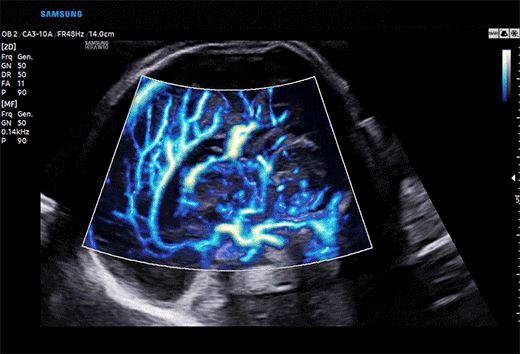

利器3:MV-Flow銳微成像、LumiFlow銳彩成像技術可非常靈敏顯示微小血管和超低速血流,清晰顯示胎兒顱內靜脈系統,配合對胎兒顱內竇匯(TH)的顯示可作為評估小腦幕位置改變的間接征象。